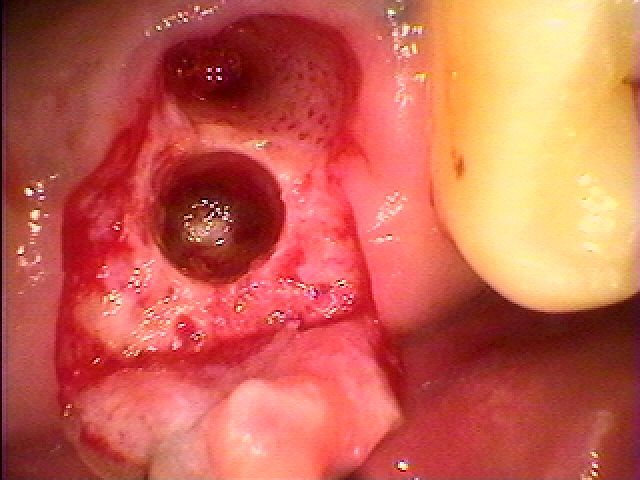

抜歯を行いました

抜歯を行いました